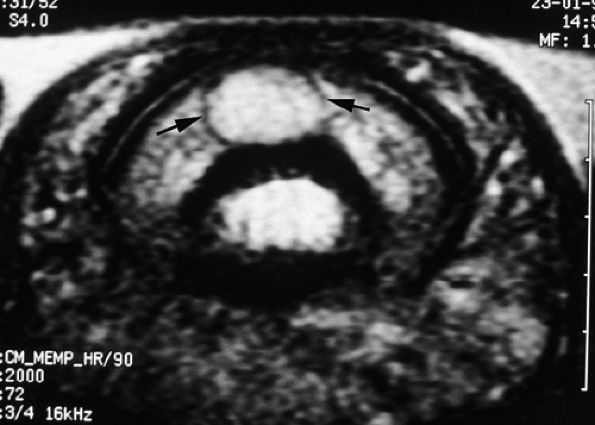

and axial MR images directly depict the tear as a thickening and a defect of the pulley (Fig. 11.55), sagittal images, which display the indirect sign of bowstringing, are more sensitive, particularly with imaging performed in forced flexion (Fig. 11.56).

FIGURE 11.55 ● Rupture of A2 pulley of the fourth finger. Sagittal (A) and axial (B) post-contrast T1-weighted images show the tear of the A2 pulley on the midline (black arrowheads) with a palmar dislocation of the flexor tendon. The pulley (white arrow and arrowhead) is now deeply located beneath the flexor tendons. Note the integrity of the A1 pulley (black arrow).